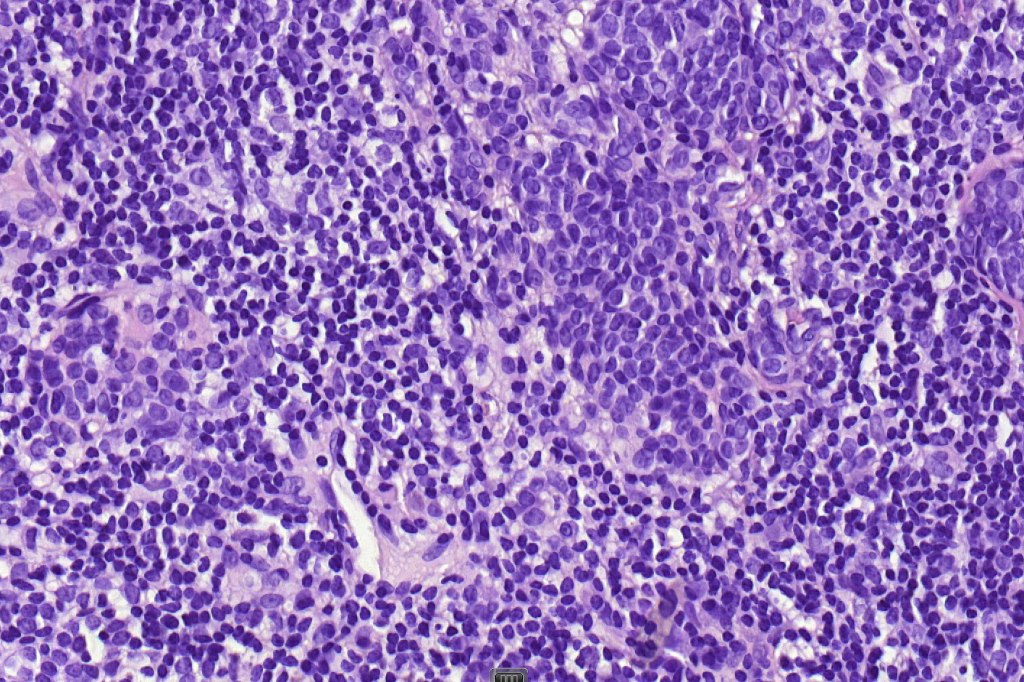

•Usually compound nevus with intense infiltration by lymphocytes, histiocytes and occasional plasma cells, in particularly florrid examples immunohistchemistry may be necessary to identify the nevus cells

•CD8+ve>CD4+

•CD20 +ve to a much minor extent

. Sometimes prominent numbers of Langerhans cell

•Mitoses can be seen in the lymphocytes but not the nevus cells